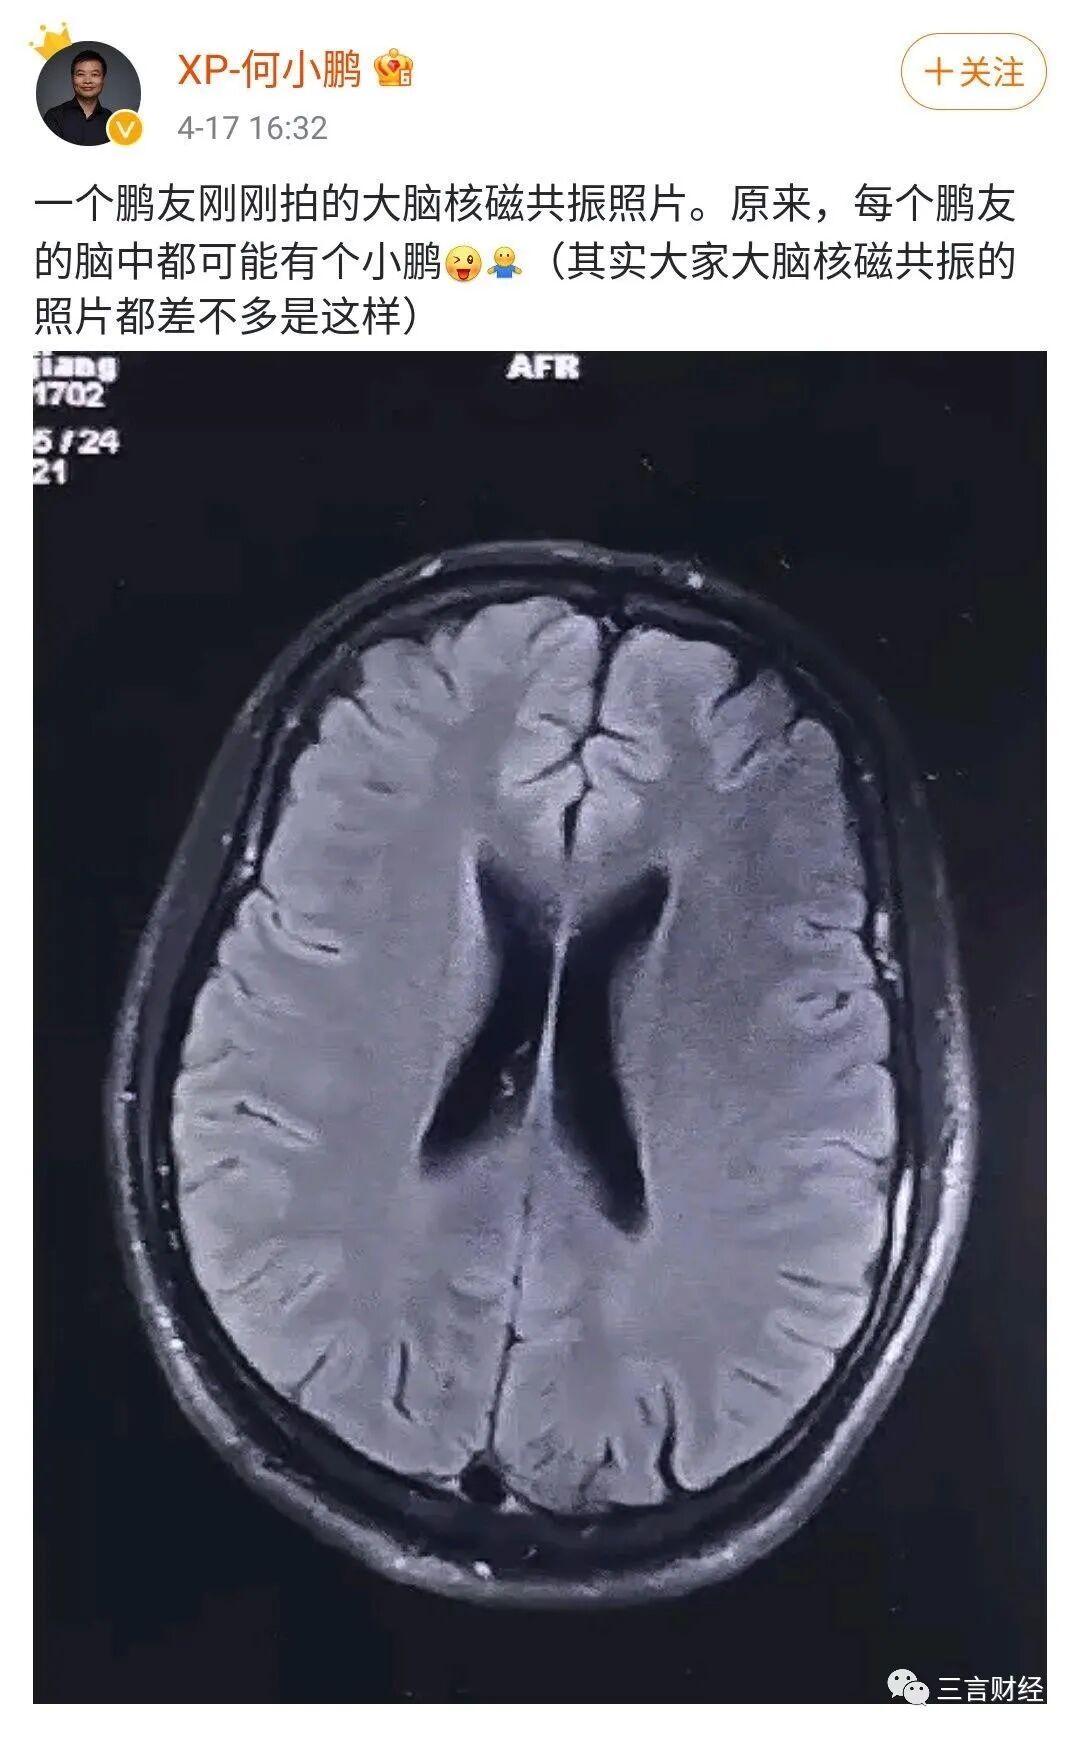

去年4月份,何小鹏用车主的脑部核磁图做宣传,也是脑洞大开,当时引发广泛争议,后来何小鹏也主动删了该条微博。